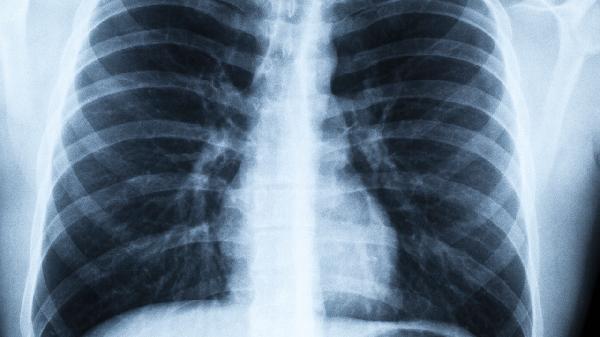

塵肺病患者應(yīng)嚴格避免繼續(xù)接觸粉塵環(huán)境,戒煙并減少呼吸道刺激。保持居住環(huán)境清潔,定期開窗通風(fēng)。適當(dāng)進行呼吸功能鍛煉如縮唇呼吸、腹式呼吸等。注意保暖預(yù)防呼吸道感染,均衡飲食保證營養(yǎng)攝入。定期到醫(yī)院進行肺功能檢查和胸部影像學(xué)復(fù)查,遵醫(yī)囑規(guī)范用藥治療。出現(xiàn)癥狀加重時應(yīng)及時就醫(yī),避免延誤病情。